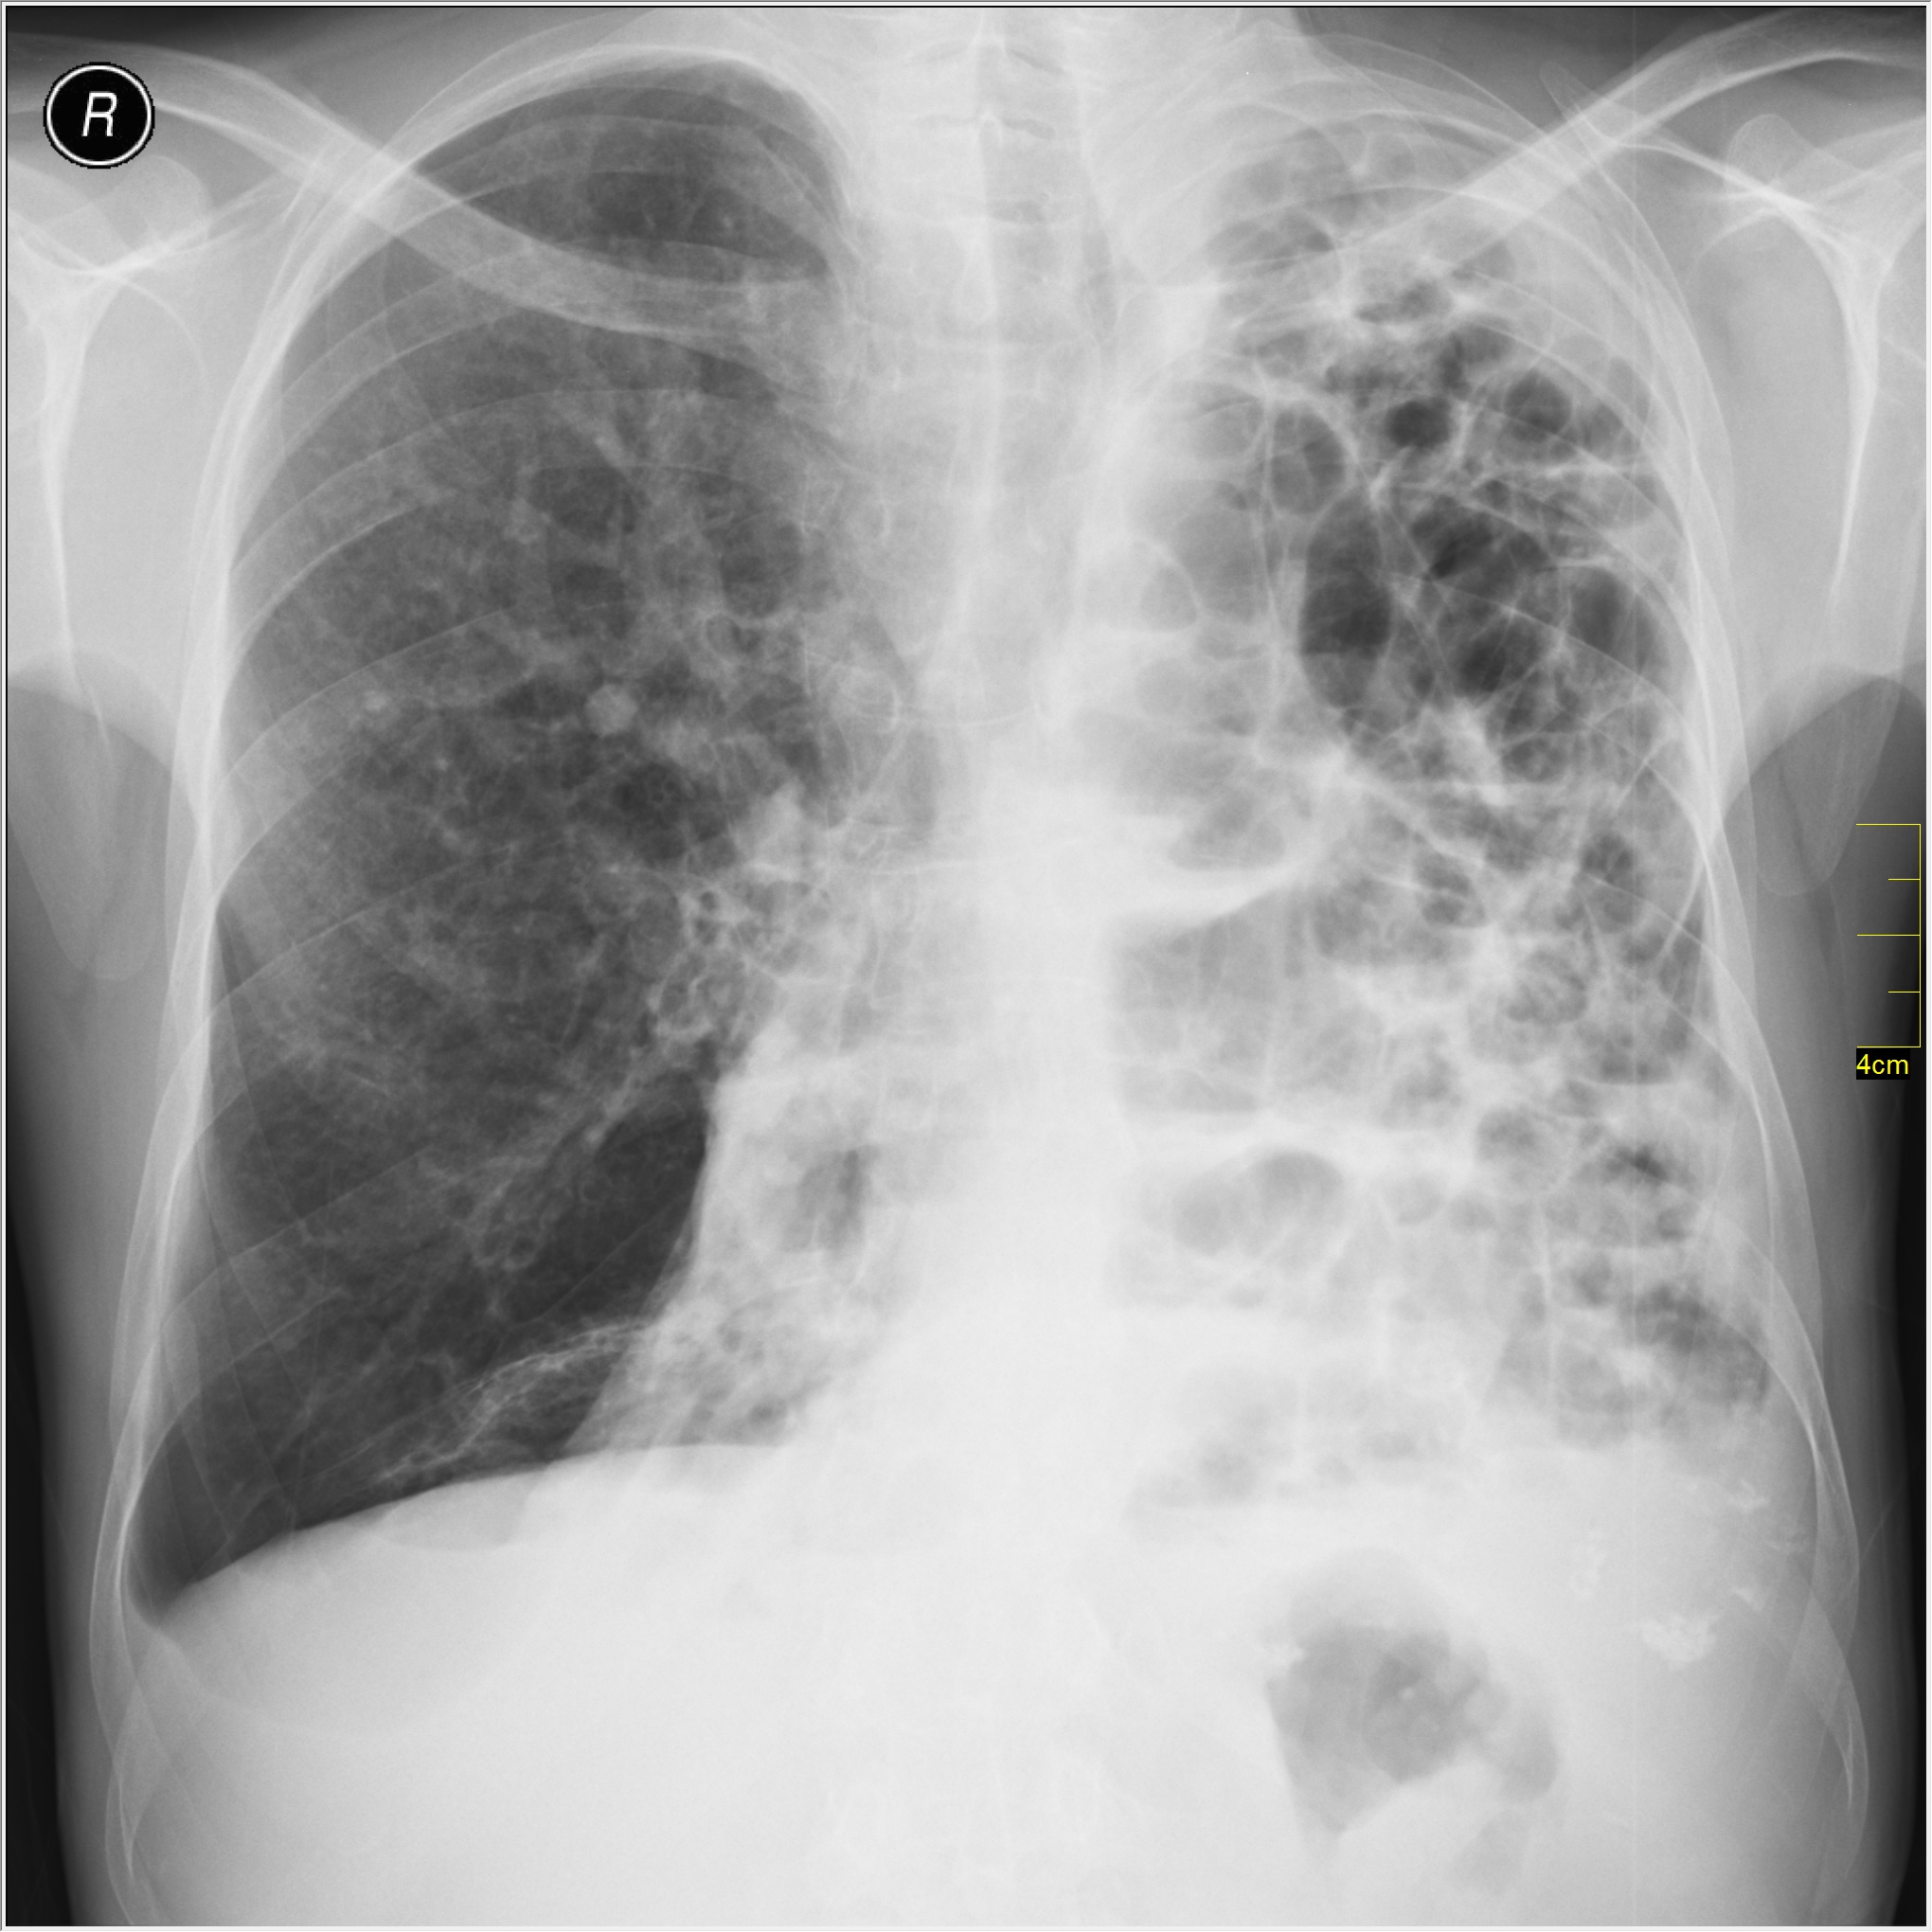

Поражение легких является одним из основных симптомов коронавируса (COVID-19). В данной статье представлены фото рентгеновских снимков, которые позволяют визуально оценить состояние легких при этом заболевании.

Коронавирус пневмония рентген

Рентген легких пневмония коронавирус

На фотографиях рентгеновских снимков видно, как вирус воздействует на легочную ткань. Характерные признаки поражения легких включают пятна, инфильтраты и наличие жидкости внутри легочных альвеол.

Фото рентгеновских снимков помогают врачам и специалистам визуально определить степень поражения легких и принять соответствующие меры лечения и поддержки пациента.